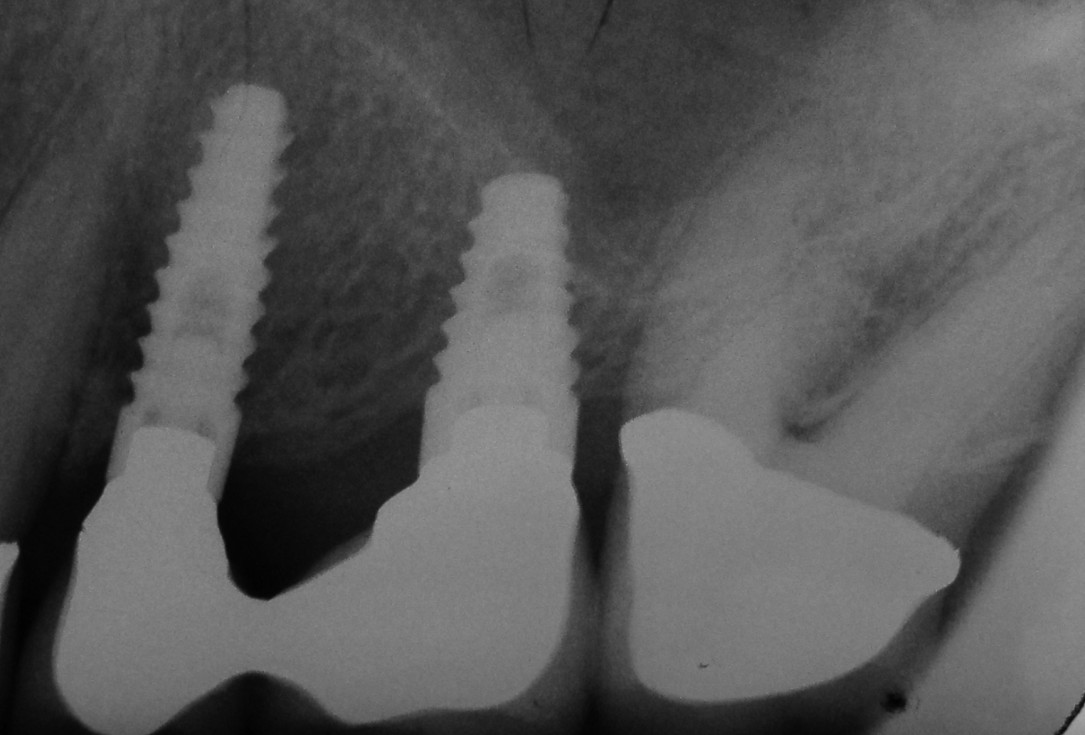

01/06 - Pre-operative radiograph.

Treatment of a periodontal bone defect adjacent to an edentulous site using Straumann® Emdogain® - Prof. Dr. P. Windisch